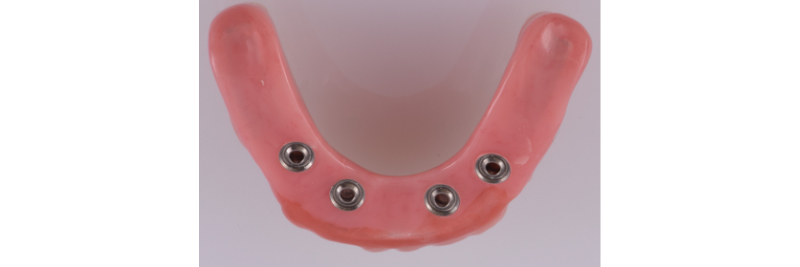

Front view of processed and polished implant hybrid prosthesis on the master cast.

Intaglio surface of the processed and polished implant hybrid prosthesis.